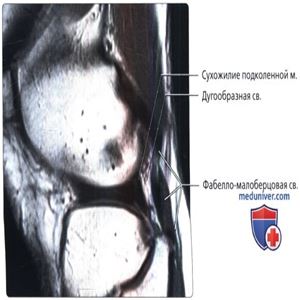

Продольная МР-томограмма, взвешенная по протонной плотности: фабелла с рельефной фабелло-малоберцовой связкой. Размеры фабелло-малоберцовой и дугообразной связок должны быть обратно пропорциональны. При отсутствии фабеллы (и, поэтому, фабелло-малоберцовой связки) хорошо визуализируется дугообразная связка. У этого пациента определяется увеличенная фабелло-малоберцовая связка, а дугообразная связка не видна.